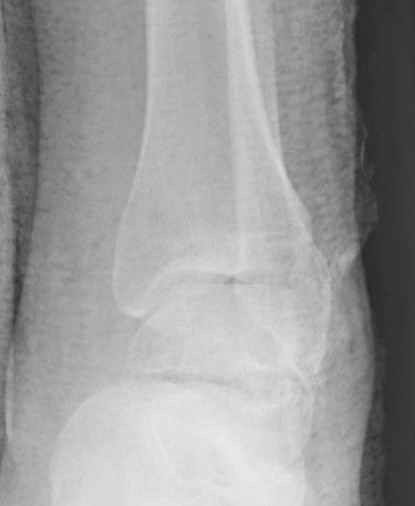

Вдогонку по поводу перелома таранной кости, больная 81, не страдает диабетом, перелом закрытый, в первый же день поступления ограничились временным наружным фиксатором (как на снимке).

За пару недель насчитал 5 больных с переломом таранной кости, из них двое с двусторонним повреждением.

Из-за отека на стопе тактика лечения у всех была

одинаковая: временная наружная фиксация до спадения отека, при изолированных переломах они выписывались домой и через дней 7 госпитализировались на оперативное лечение.

Примеры на снимке...